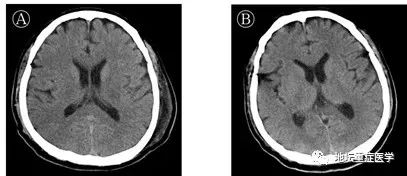

《方案》称,患者脑组织充血、水肿,部分神经元变性。北京地坛医院3月4日公布的消息称,临床发现患者出现意识障碍,一定要考虑病毒可能攻击中枢神经系统。